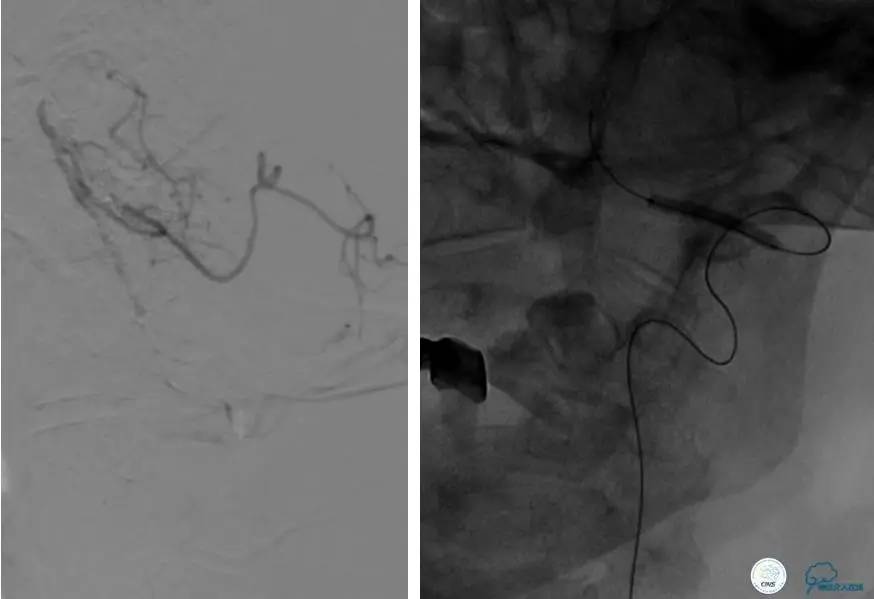

造影评价血管、判断闭塞段,微导丝小心穿过闭塞段,微导管造影,交换技术,球囊扩张,Enterprise支架。在后扩张时导丝刺破M3段血管,蛛网膜下腔出血(SAH)。

微导管进入破裂血管,栓塞弹簧圈1枚,出血停止,结束手术。继续双抗,术后2天肌力2级,神经功能恢复明显加快。

术后即刻和6天后CT,患者无明显临床症状。

半年后复查造影,无支架内再狭窄,可见弹簧圈,患者恢复至自己柱杖行走。